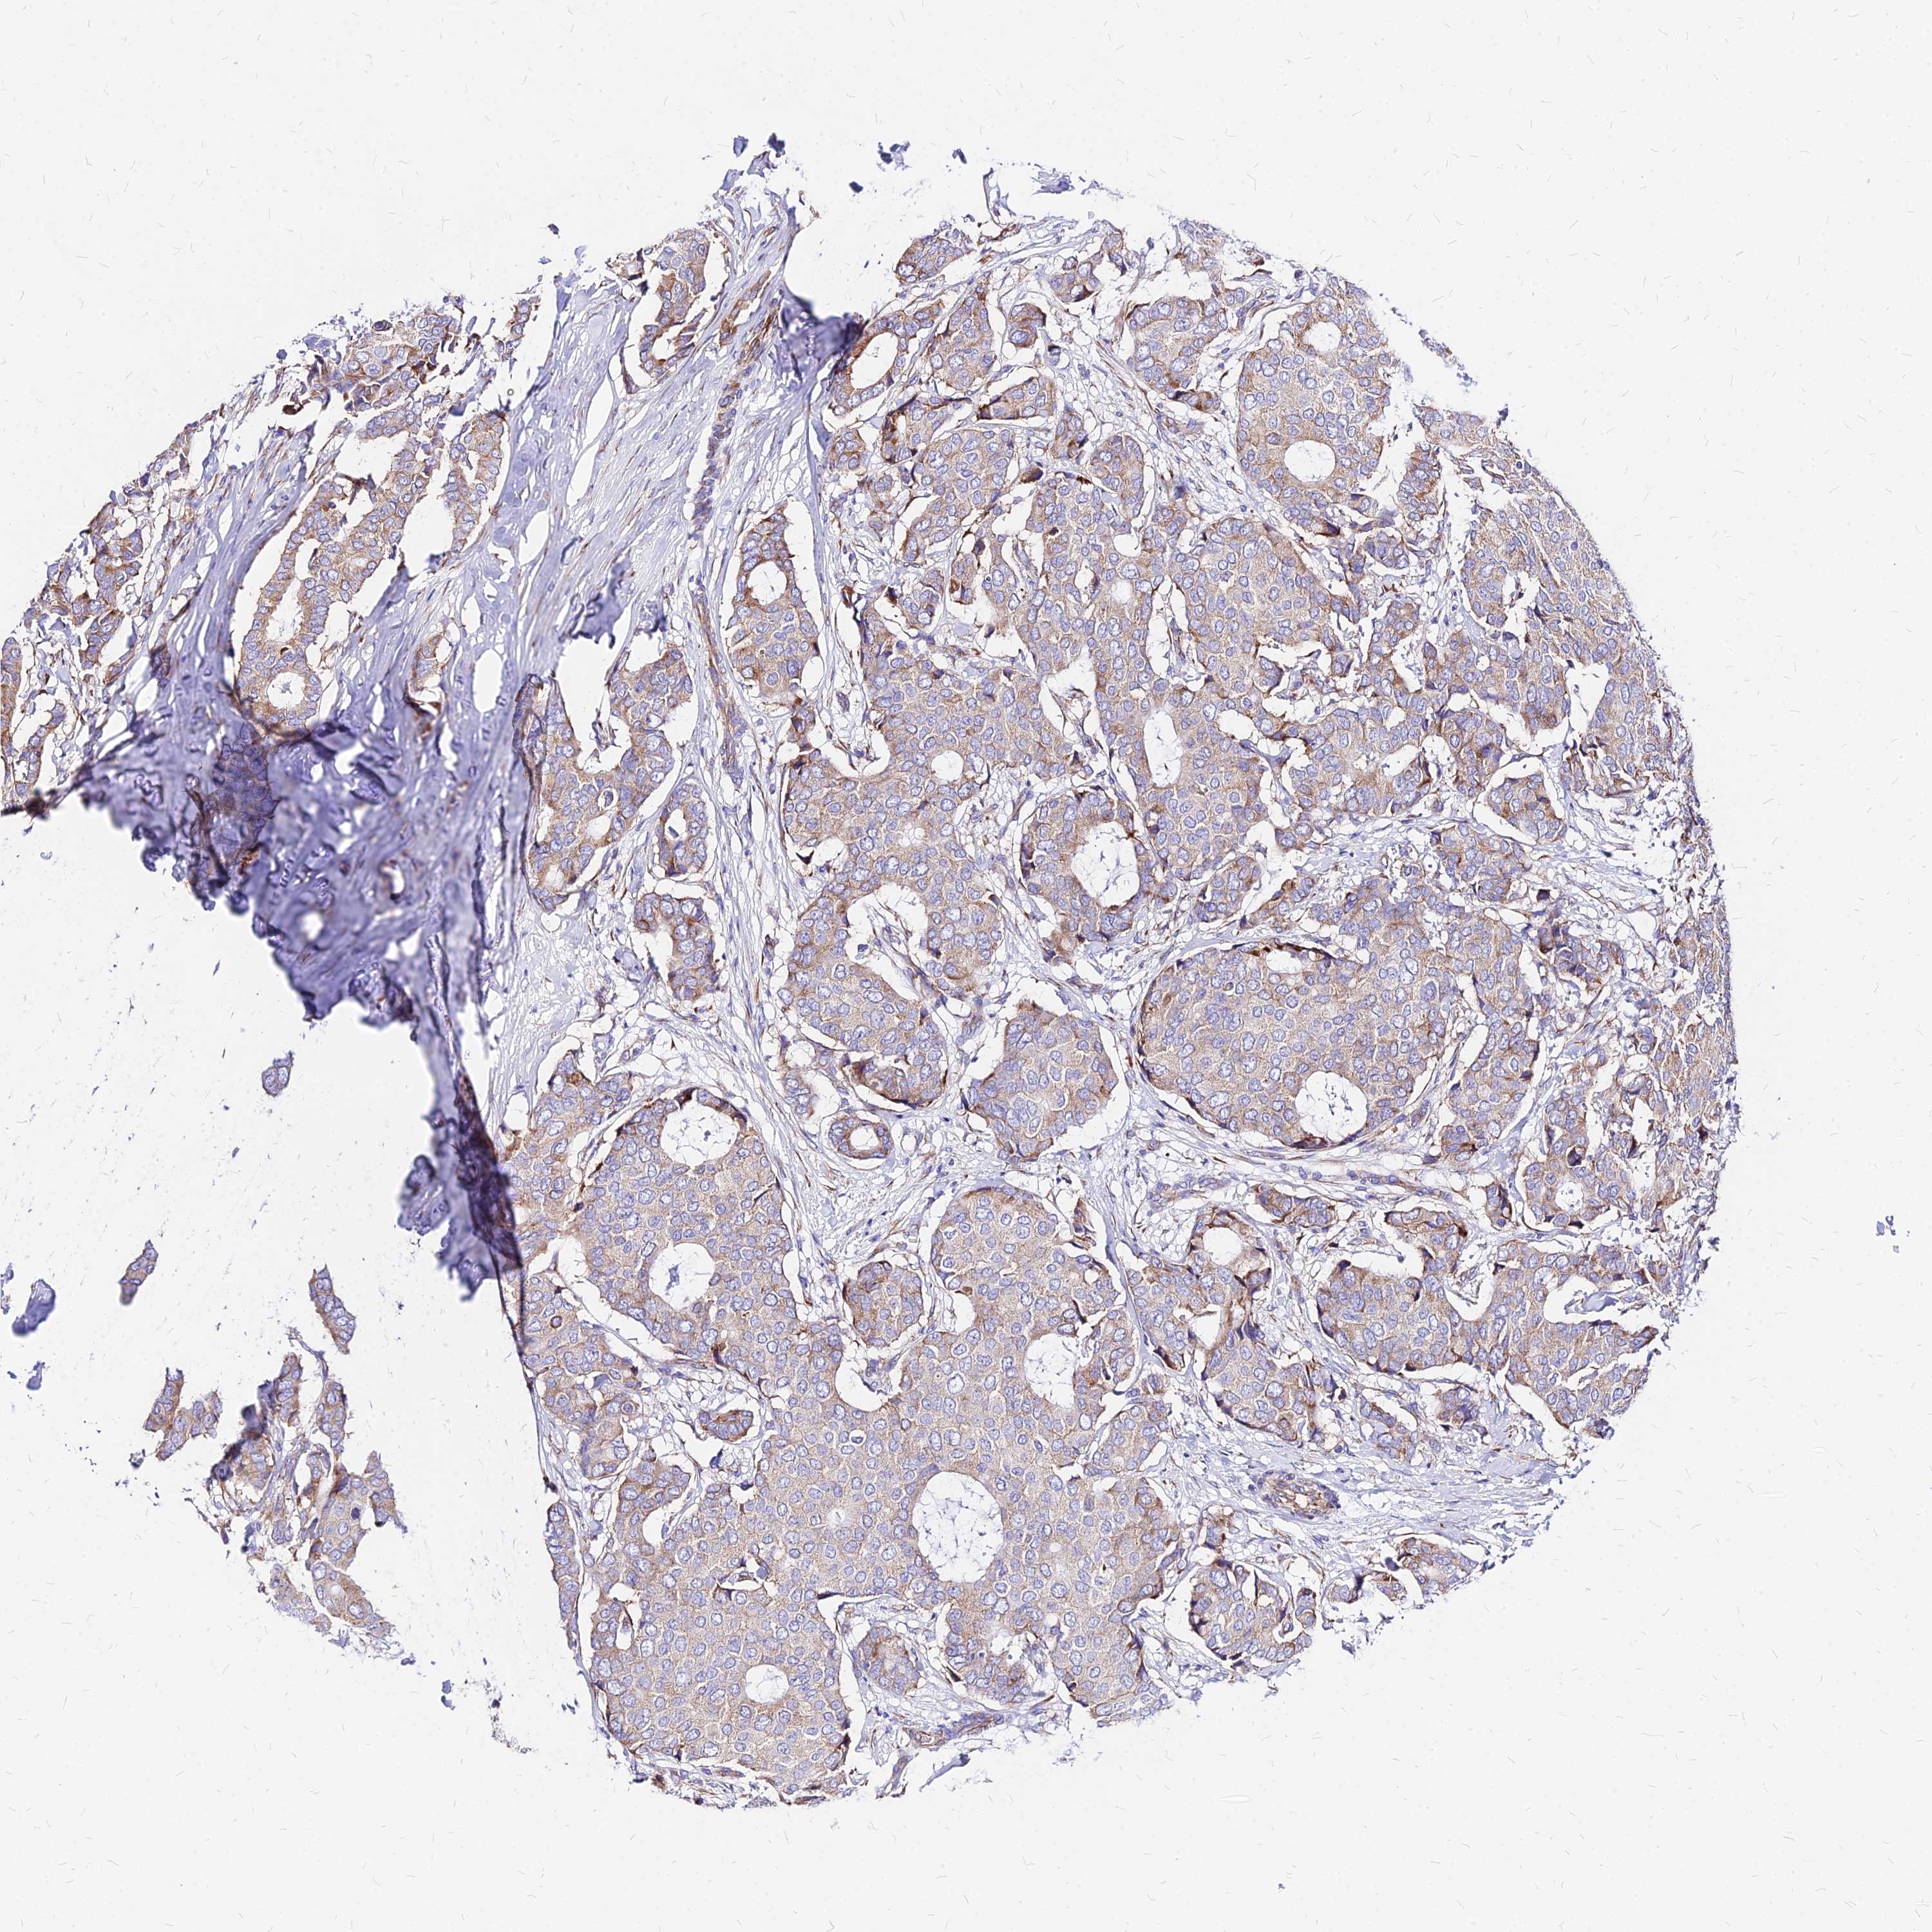

CANCER BREAST CANCER Show tissue menu

BRCA TCGA BRCA VALIDATION PROTEIN EXPRESSION